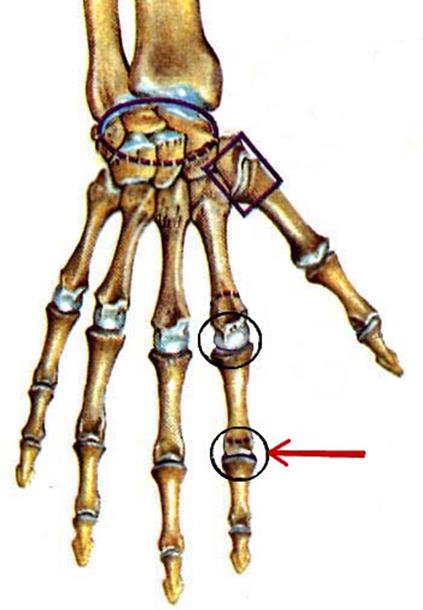

S: Числом 10 обозначена os ### (латинский язык).

S: Цифра 5 обозначает ossa ### (латинский язык).

S: Цифрой 8 обозначена os...

S: Числом 12 обозначена os...

S: Числом 13 обозначена os...

S: Цифра 3 указывает на...

S: Цифра 2 указывает на …

S: Цифра 1 указывает на....

S: Стрелка указывает на art....

S: Стрелка указывает на art....

S: Стрелка указывает на art....

S: Стрелка указывает на art....

S: Стрелка указывает на art....

S: Стрелка указывает на art....

S: Стрелка указывает на art....

S: Стрелка указывает на art....

S: Стрелка указывает на art....